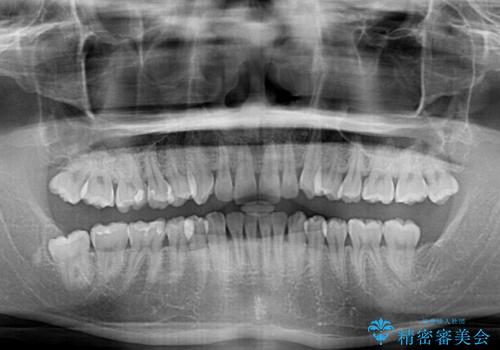

事前に親知らず4本を抜歯し、多少歯列を後方に移動できるように準備をした上で、なるべく歯と歯の間を削ることなくデコボコを解消できるように計画しました。

途中、以前大きなむし歯で処置をした歯が痛み出し、根管治療が必要となったため、根管治療とオールセラミッククラウンによる補綴治療を行い、その後にインビザラインによる仕上げの歯列移動を行い、無事に治療を終えることができました。